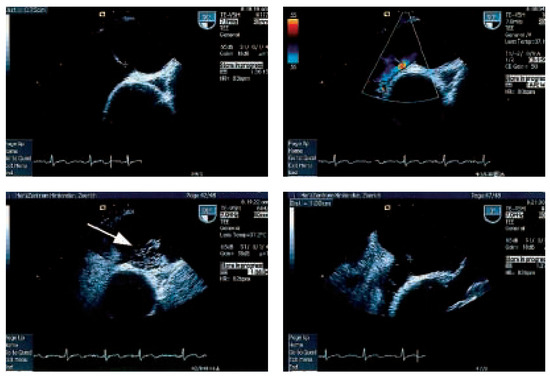

In der transthorakalen Echokardiographie fand sich eine linksventrikuläre Hypertrophie bei normaler systolischer Funktion. Zusätzlich bestand eine minime Mitralinsuffizienz und Aorteninsuffizienz. Es fand sich ein Vorhofseptumaneurysma mit einem kleinen Shunt auf Vorhofebene (Figure 1). Der pulmonal-arterielle Druck war entsprechend dem Doppler-echokardiographisch erhobenen Druckgradienten zwischen rechtem Ventrikel und rechtem Vorhof (30 mm Hg) nicht erhöht. In der anschliessenden transösophagealen Echokardiographie (Figure 2) konnte ein ASD Typ II im Bereich des Foramen ovale mit einem bidirektionalen Shunt, einem Vorhofseptumaneurysma und einer persistierenden Eustach-Klappe dargestellt werden.

Figure 2.

TEE-Untersuchung mit ASD II und Shunt im Farbdoppler und der Gabe von Bubbles mit Rechts-Links-Shunt unter Valsalva (Pfeil).